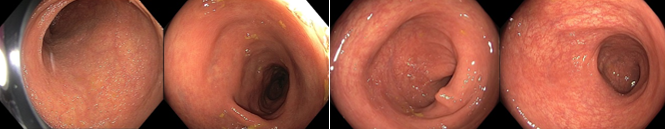

018/2 Slizniční zhojení. Monoterapie vedolizumabem

2022/9 klinická, laboratorní i endoskopická remise

Slizniční zhojení

Histologie: lehká porucha architektoniky krypt, může se jednat o pozánětlivé změny. Jiné histopatologické změny přítomny nejsou.